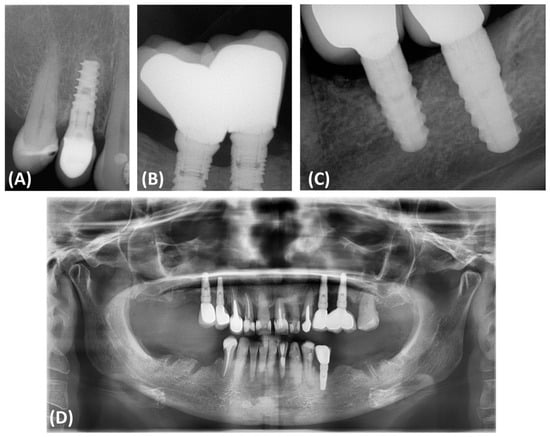

2.4. Assessment of Radiographs and Assessment of Bone Attenuation